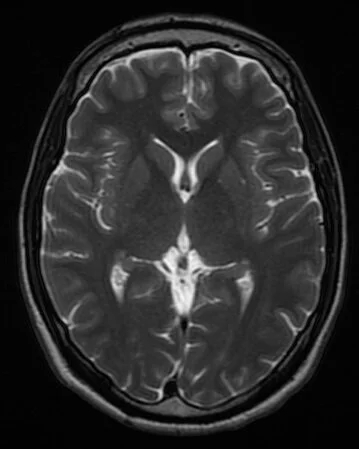

MRI scans

MRI scan of a healthy brain. Credit: Novaksean, CC BY-SA 4.0 https://creativecommons.org/licenses/by-sa/4.0, via Wikimedia Commons

• Magnetic resonance imaging (MRI) scanners use radio waves in the presence of a strong magnetic field to produce cross-sectional images of the brain.

• Higher quality and have a higher resolution than CT scans.

• Also used in medical diagnosis because they can be used to visualise damaged or diseased parts of the brain. For example, MRI scans can be used to indicate the presence of a brain tumour, which shows up as a lighter colour on an MRI scan.

• Doctors can determine the size and location of the tumour and decide on the best treatment option to take. Just like CT scanning, the function of brain regions can be inferred by matching up a patient’s symptoms with areas of brain damage.